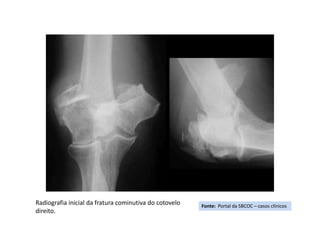

Radiografia inicial da fratura cominutiva do cotovelo

Fonte: Portal da SBCOC – casos clínicos

• Resumo do caso: Paciente do sexo feminimo, 67 anos, portadora de AR, que

• Paciente (dados): Feminina, 67 anos

• História: Paciente com Artrite Reumatóide, fazendo uso de corticóides há mais

de 20 anos. Há 5 dias queda sobre o cotovelo D. ; Frat. exposta puntiforme.

Foi atendida em outro serviço onde instalaram o fixador externo após a limpeza

e desbridamento cirúrgico.

• Diagnóstico(s): Fratura Supra-intercondileana do cotovelo direito

• Tratamento(s): Retirada do fixador externo e artroplastia do cotovelo Direito.